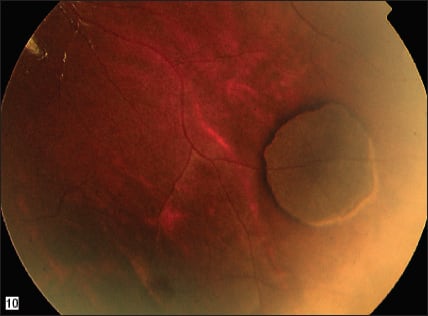

In 2005, two years after this patient's presentation, the lesion appeared to be stable with no noted change (Figures 2 and 3). In 2008, the patient developed lacunae within the lesion (Figure 4). In 2009, slight growth of the lesion and the lacunae were detected (Figure 5). RP

Figures 2 and 3. Two years after the initial presentation, the lesion appears stable.